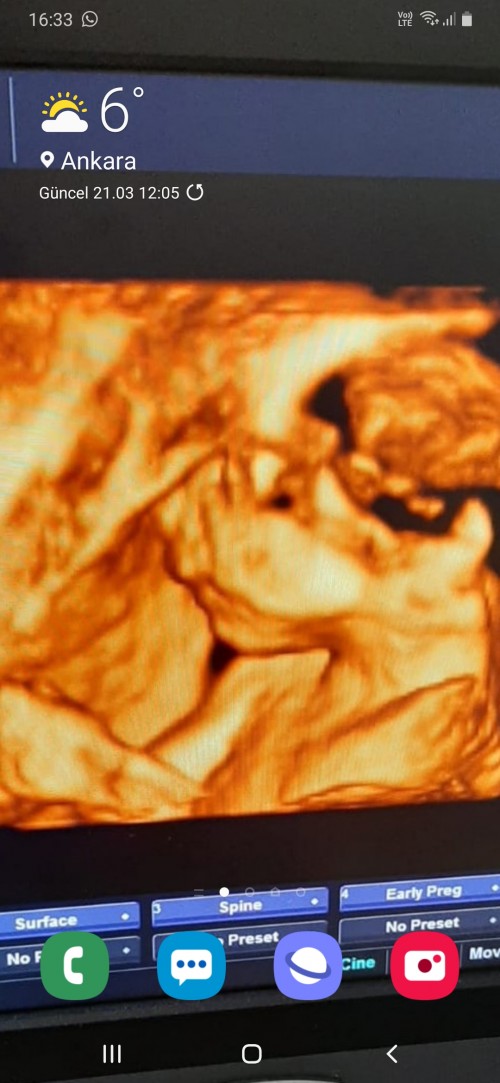

image

benimki boyle☺️☺️